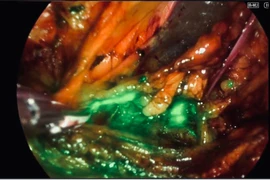

Bệnh nhân 36 tuổi bị viêm ruột thừa vỡ, phải phẫu thuật cấp cứu. Khuyến cáo không chủ quan khi có đau bụng kéo dài, để tránh biến chứng nguy hiểm.

Bệnh nhân 36 tuổi bị viêm ruột thừa vỡ, phải phẫu thuật cấp cứu. Khuyến cáo không chủ quan khi có đau bụng kéo dài, để tránh biến chứng nguy hiểm.

Ca phẫu thuật bằng kỹ thuật mới giúp giảm biến chứng, rút ngắn thời gian hồi phục, mở ra hướng đi mới trong điều trị ung thư nội mạc tử cung.